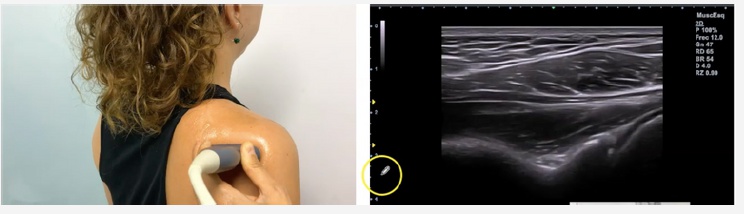

Cuando un paciente acuda a consulta con signos claros de rotura del labrum posterior, podrás verlo a través de tu ecógrafo.

A continuación te enseñamos cómo debe ser la exploración en la normalidad y qué imágenes puedes encontrarte en un paciente con el labrum afectado.

ECOGRAFÍA DE UN LABRUM SANO

Vas a tener en cuenta el siguiente corte de referencia.